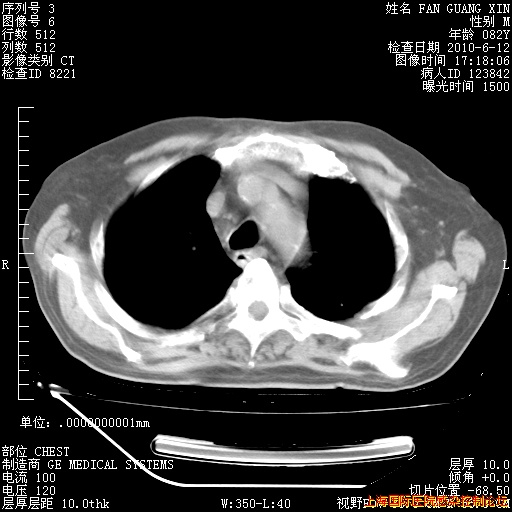

补发6月12日肺部CT肺窗

6月12日肺窗